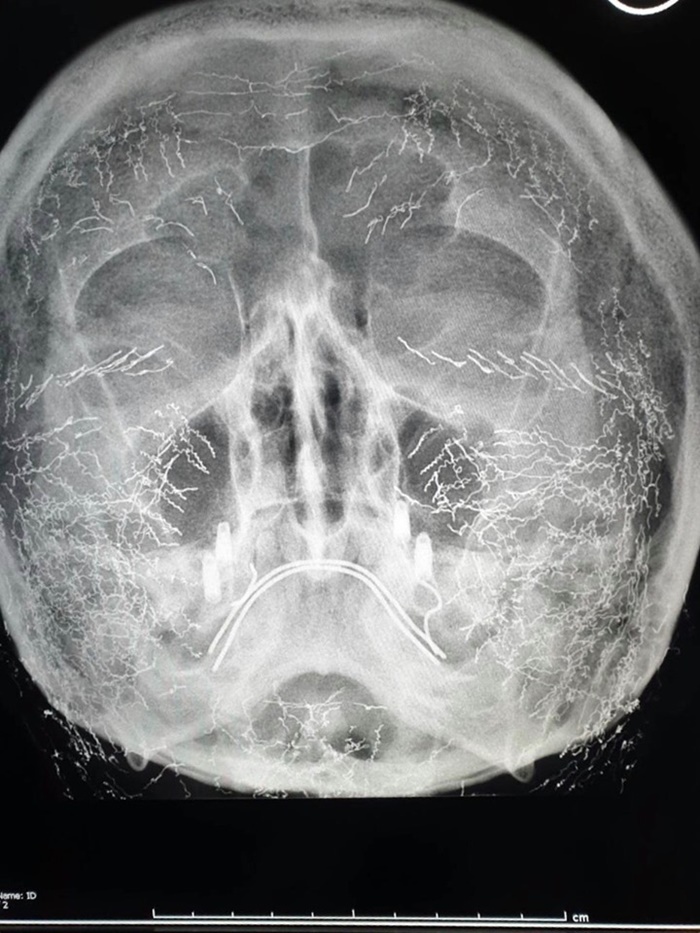

วันที่ 1 มิถุนายน 2562 เฟซบุ๊ก Suthipong Treeratana ของ นพ.สุทธิพงษ์ ตรีรัตน์ แพทย์ผู้เชี่ยวชาญด้านการศัลยกรรม ได้มีการโพสต์ข้อความเตือนคนที่คิดจะทำการร้อยไหมด้วยโลหะ เช่น ทอง ว่าอาจเสี่ยงอันตราย เพราะไหมเหล่านี้จะฝังอยู่บนใบหน้าเป็นจำนวนมาก ถ้าหากเกิดมีเหตุจำเป็นต้องเข้ารับการตรวจคลื่นแม่เหล็กไฟฟ้า หรือ เอ็มอาร์ไอ (MRI - Magnetic Resonance Imaging) จะมีความเสี่ยงอันตราย เพราะสนามแม่เหล็กเหนี่ยวนำโลหะ ให้เกิดความร้อน และจะทำให้หน้าไหม้ได้ทั้งใบหน้า

"คนเราต้องมีโอกาสทำ MRI บ้างในชีวิต เช่น ปวดคอ ดูกระดูกต้นคอ ซึ่งเลี่ยงไม่ได้ และไม่มีรังสีแพทย์คนไหนจะทราบมาก่อน ถึงทราบแล้วจะทำไงดี ไหมเอาออกไม่ได้ แต่ MRI ก็ต้องทำ"

สำหรับการผ่าตัดหรือการรักษาทางการแพทย์ที่มีการใช้สกรูโลเหล็ก หรือลวด

ส่วนนี้ไม่มีปัญหา

เพราะเป็นอุปกรณ์ทางการแพทย์ที่ออกแบบมาเพื่อให้สามารถใช้งานกับเครื่อง MRI

ได้อยู่แล้ว ซึ่งจะแตกต่างกับไหมโลหะที่ใช้ร้อยไหมยกกระชับใบหน้า